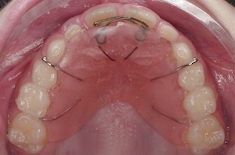

The wire springs are attached to a smooth, pink, plastic supporting plate which is held securely in the mouth by wire clasps.

The removable appliance pictured on the right was used to push the two front teeth forwards.